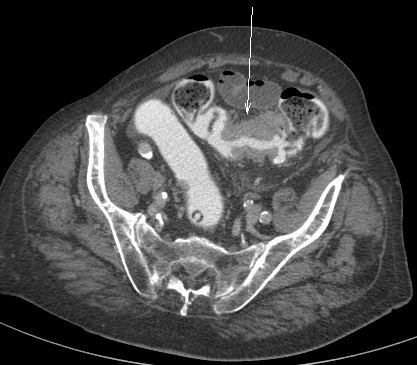

24

Le patient a une diverticulite. Devant persitance fièvre et augmentation du sd inflammatoire à 48h on réalise le TDM suivant. Vu la taille de l’abcès (>5 cm on va dire), quelle CAT?

A

drainage de l’abcès: ponction percutanée écho ou scanno-guidée; OU drainage chirurgical si percut impossible (avec RDC à distance)